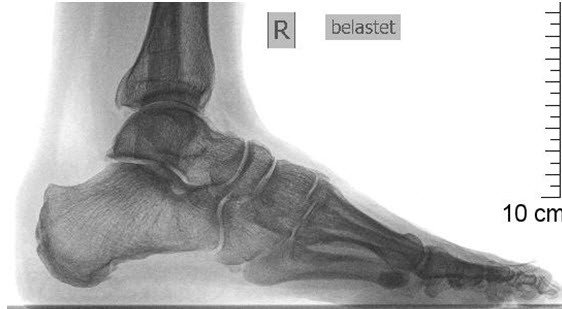

Die 59-jährige, sportliche Patientin litt seit längerem an starken Druckbeschwerden in geschlossenen Schuhen sowie belastungsabhängigen Schmerzen an der Rückseite der rechten Ferse. Ursache war ihr ausladendes Fersenbein mit nun chronischer Entzündung im Ansatzbereich der Achillessehne, was als Haglund-Ferse bezeichnet wird.

Nach Versagen der konservativen Therapien und mittlerweile grossem Leidensdruck wurde als Lösung die Durchführung einer Kelly-Keck-Osteotomie vorgeschlagen. Hierbei handelt es sich um eine Operation, bei welcher zur Verkleinerung des Fersenbeins ein Knochenkeil aus diesem entnommen wird. Die Druckentlastung leitet das Abheilen der Entzündung ohne Eingriff an der Achillessehne selbst ein, was in der Regel zur Beschwerdefreiheit führt.

Nach diesem Eingriff ist eine Ruhigstellung des Fusses in einer Unterschenkelschiene mit Teilbelastung von 15 kg an Gehstöcken für sechs Wochen notwendig, damit der mit Klammern fixierte Knochen zusammenwachsen kann. (Abb. 2) Der Eingriff, der in Lokalanästhesie (Fussblock) durchgeführt werden kann, verlief komplikationslos; die Patientin konnte plangemäss nach zwei Nächten im Spital entlassen werden.